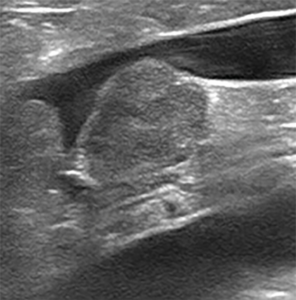

Se añaden dos dosis de hidralazina 0,5 mg/kg/BID por vía oral. Se realiza una ecografía completa y se aprecia: hipertrofia concéntrica de septo interventricular y pared libre ventricular izquierda, atrio izquierdo gravemente dilatado (ratio LA/Ao: 3,02), insuficiencia mitral de 7,5 m/s y disfunción diastólica grado III (imagen 3).

Ecocardiografía con hipertrofia concéntrica difusa de septo interventricular y pared libre ventricular izquierda, grave dilatación de atrio izquierdo, flujo transmitral restrictivo compatible con disfunción diastólica grado III e insuficiencia mitral de alta velocidad que sugiere hipertensión arterial sistémica.

Imagen 3. Ecocardiografía con hipertrofia concéntrica difusa de septo interventricular y pared libre ventricular izquierda, grave dilatación de atrio izquierdo, flujo transmitral restrictivo compatible con disfunción diastólica grado III e insuficiencia mitral de alta velocidad que sugiere hipertensión arterial sistémica.